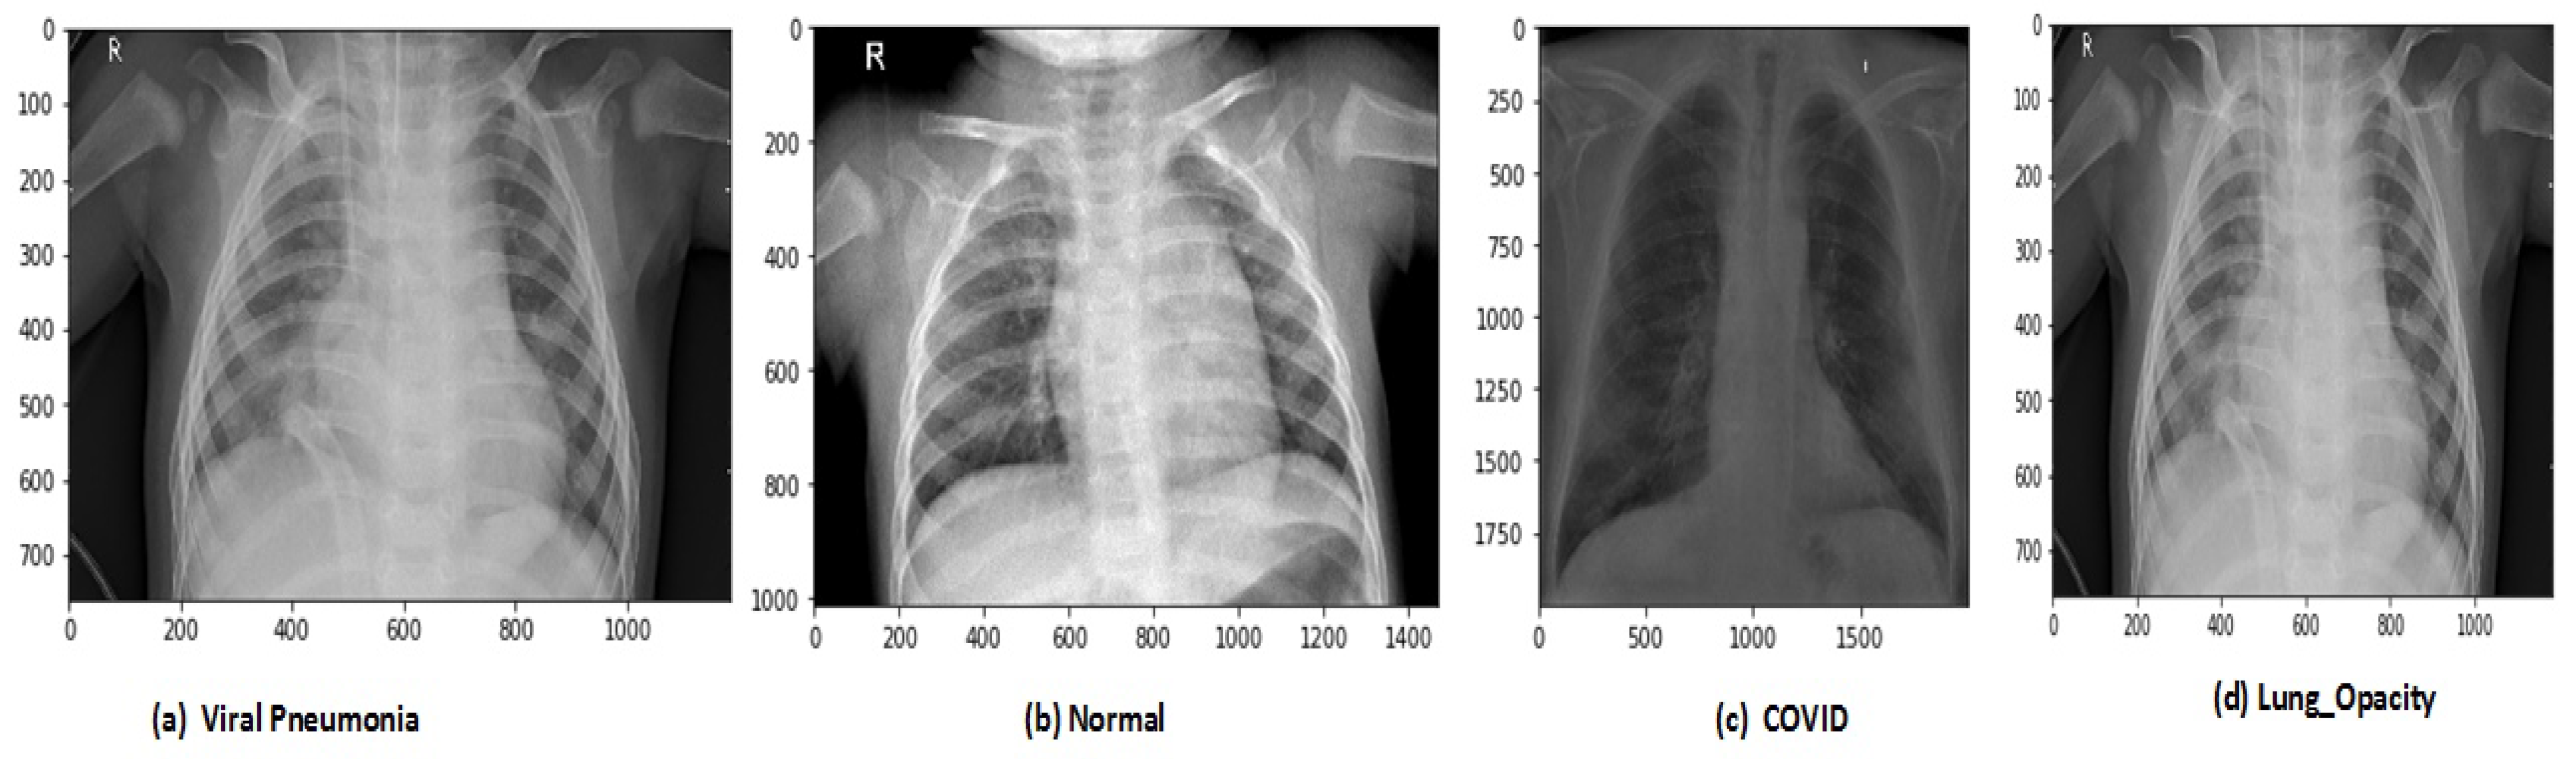

After data augmentation, the images in the new dataset are 12,864. The proposed model has trained on original and augmented data sets, respectively, for all experiments. The holdout cross-validation method has used for the training and validation process in the proposed model because the data sets are now large enough so it will not make computational complexity problems and model will fit exactly and will generate high performance. The images of CRD and CXI datasets are shown in Figure 3 and Figure 4.

Figure 3.

Types of chest X-ray images in CRD data set.

Two data set are used in this research for the evaluation of the proposed R2DCNNMC model. Before applying these data sets in the model we need to perform so pre-processing operations on both data sets that model suitable trained for effective performance. The COVID-19-Radiography-Dataset (CRD) is a data set of chest X-ray images for COVID-19 positive cases along with Normal, Viral Pneumonia, and Lung Opacity. This data set included 3616 COVID-19 positive cases, 10,192 Normal, 6012 Lung Opacity, and 1345 Viral Pneumonia images. The total images in the data set are 21,165.